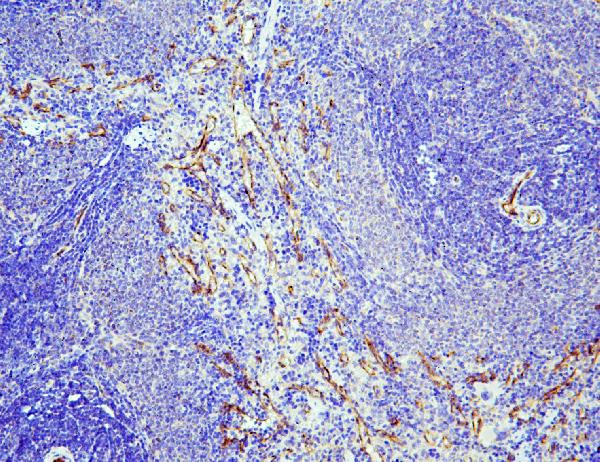

IHC analysis of eNOS/NOS3 using anti-eNOS/NOS3 antibody (A01604-2).

eNOS/NOS3 was detected in a paraffin-embedded section of human lung cancer tissue. Biotinylated goat anti-rabbit IgG was used as secondary antibody. The tissue section was incubated with rabbit anti-eNOS/NOS3 Antibody (A01604-2) at a dilution of 1:200 and developed using Strepavidin-Biotin-Complex (SABC) (Catalog # SA1022) with DAB (Catalog # AR1027) as the chromogen.